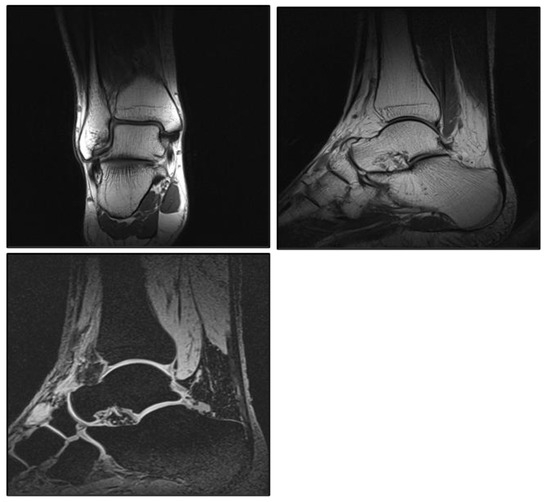

Figure A5.

Examples of the quantitative representation of the tibial and talar articular surfaces.